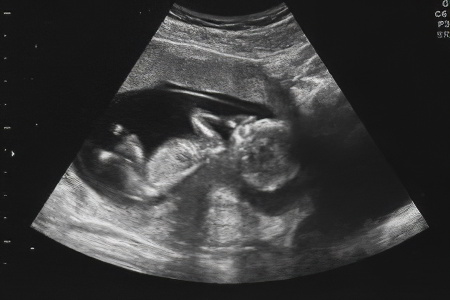

УЗИ, проведенное на сроке 20-24 недели, позволяет оценить следующие аспекты течения беременности:

• Точный срок гестации;

• Соответствие размеров плода сроку беременности;

• Возможные аномалии развития (например, порок сердца);

• Объем околоплодных вод;

• Состояние плаценты, миометрия матки и риск предлежания;

• Пол будущего ребенка.